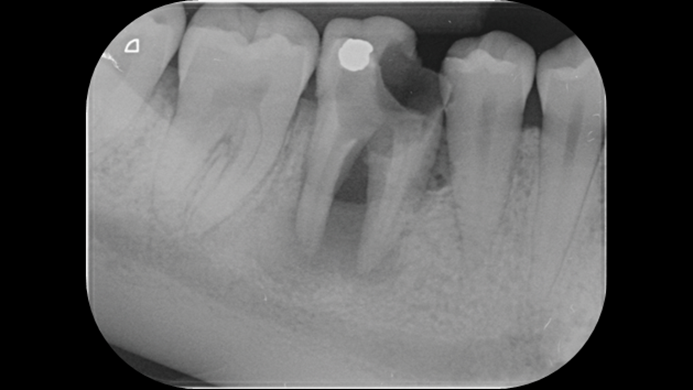

Clinical case: # 46 implant placement & GBR using i-Gen membrane for significant vertical resorption & mixed bone defect

- Courtesy of Dr. Iulian Filipov, Romania -

AnyRidge, mandibular posterior, i-Gen, resorption, bone defect, bone regeneration, space management, #46, GBR, Dr. Iulian Filipov

“AnyRidge KnifeThread achieves excellent stability in regenerated bone & even in only 3mm bone height!”